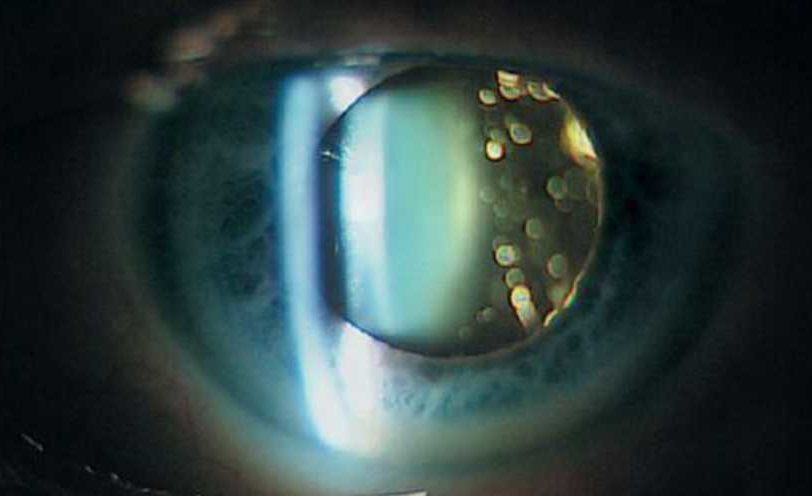

Фото

- Биомикроскопия с использованием щелевой лампы помогает выявить изменения в консистенции стекловидного тела, а также области помутнения и образования коллагеновых волокон.